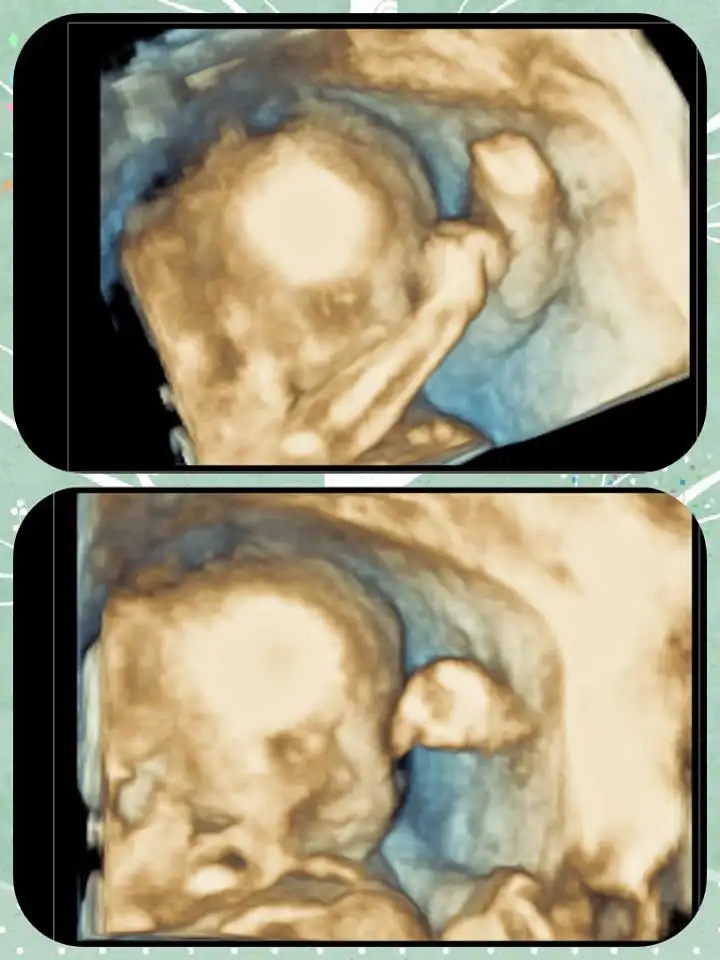

kızlar merhaba bugün biraz geç dönebildim size nasılsınız umarım herkes çok iyidir şükür ki bende öyleyim :KK73:çok mutluyum çünkü bebişimi gördüm bugün sabahtan kan verdim aç karnına sağlık ocağında sarstı beni azıcık tansyonum düştü biraz uzandıktan sonra da aşımın ilk dozu vuruldu çok şükür sıkıntım olmadı sonraa ayrıntılı ultrason çok şükür orada da hiç sıkıntı yok bebişimiz oldukça sağlıklı teyzelerine gülücük gönderdi bende ekleyeyim dedim :KK36::KK36: çok heyecan verici birşeymiş allah herkese nasip etsin inşallah:rolleyes::rolleyes:

Eklentiler

• bebişim.webp

bebişim.webp

26,1 KB · Görüntüleme: 159